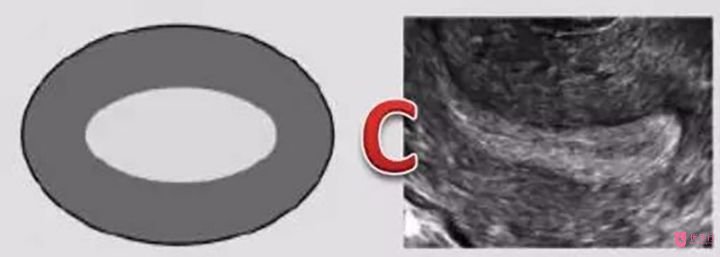

C型內(nèi)膜:常見于黃體期(即排卵后到下次月經(jīng)來潮前),厚度約10-14mm。為均質(zhì)強回聲,無宮腔中線回聲,此時“三線征”消失。